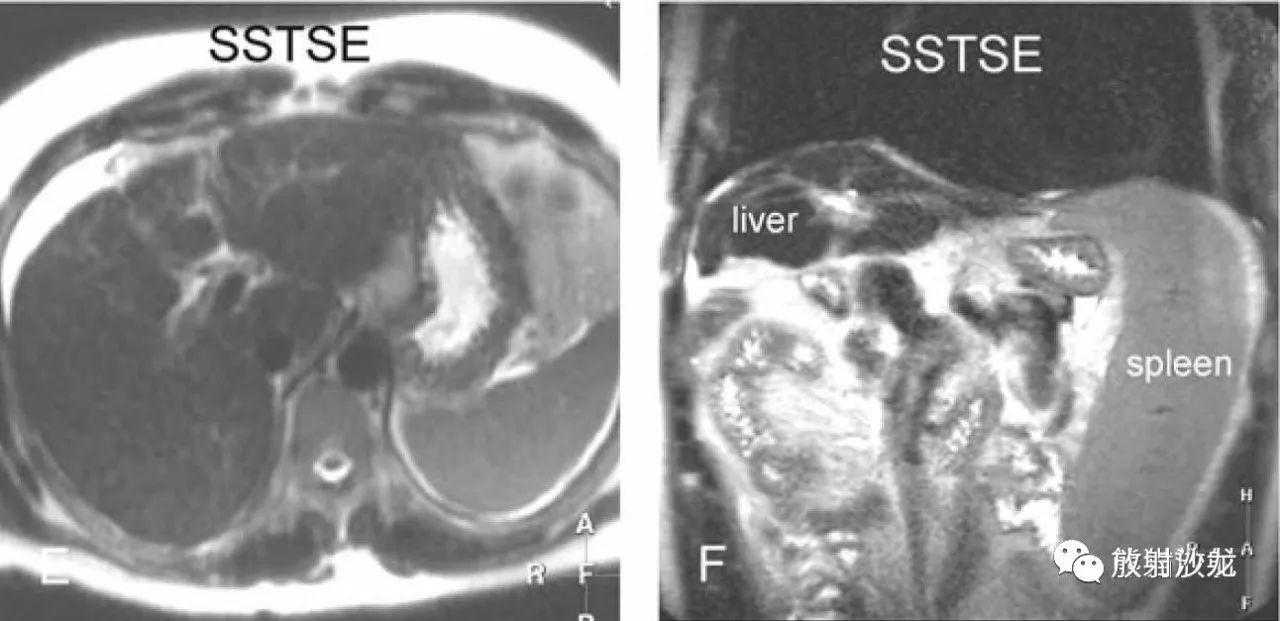

肝硬化,形态表现(来自六个不同患者):

E:T2WI,肝左内叶(IV段)萎缩;

F:冠状T2WI,肝脏萎缩,脾脏增大;

G:T2WI,肝左内叶(IV段)完全萎缩;

H:冠状T2WI,肝右叶及左外叶增生肥大。